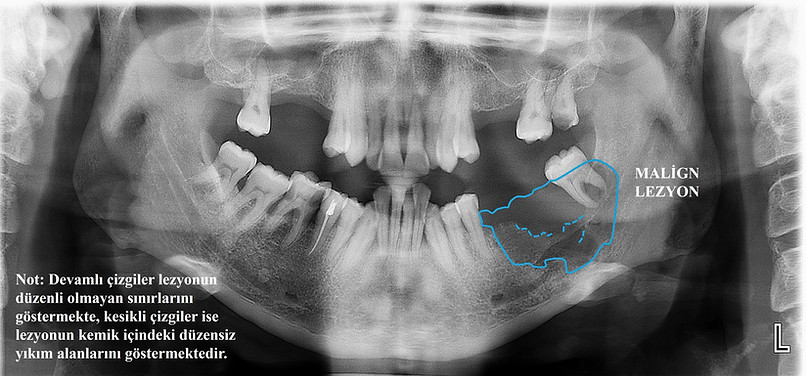

malign lezyon